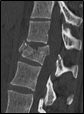

- TAC (Eskanerra)

Proba ez inbaditzailea da, baina garestiagoa eta erradiografiak egitea baino zailagoa. Jasotzen den erradiazio-dosia (X izpiak) altua da. Hezurretako arazoak behar bezala diagnostikatzen ditu, baina gutxiago alboetako ehunak. Gaur egun, 3 dimentsiotako irudiak lor daitezke eta, horiei esker, ornoen egoera hobeto uler daiteke. Biopsiak, kultiboak eta horrelakoa lortzeko gida izan daiteke. Ospitaleko medikuak erabili ohi du.